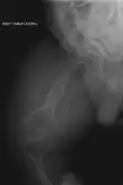

Les aspects radiographiques de l'os contribuent au diagnostic.

Diagnostic radiologique

On observe une transparence excessive des os ainsi que des déformations sur les clichés radiologiques[7]. Ces déformations sont principalement constatées au niveau de :

- la partie diaphysaire de l’os : une corticale diaphysaire mince, une crosse au niveau des os longs ainsi que la présence de plusieurs cals osseux ;

- la hanche avec une protrusion acétabulaire c'est-à-dire une malformation associant une hanche trop profonde et des amplitudes articulaires diminuées ;

- des pieds avec des pieds plats et en valgus c'est-à-dire les membres qui s’écartent vers l’extérieur par rapport à l’axe du corps ;

- des membres supérieurs avec une déformation supérieur à 30° ;

- du crâne avec des os wormiens c'est-à-dire des petits os situés à l'intérieur de divers os constituant le crâne (occiput, pariétal, temporal…) présents en nombre plus important que la normale ;

- du rachis et du thorax avec un thorax plus bombé que la normal et des modifications au niveau des vertèbres telles que des tassements de certaines vertèbres, des vertèbres biconcaves, des scolioses… Lors de fractures, le siège se situe principalement au niveau des membres inférieurs et des vertèbres.